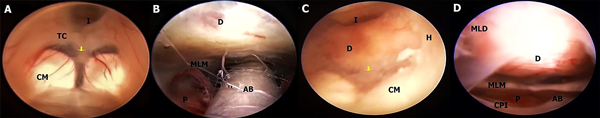

En este estudio fueron halladas 10 variedades anatómicas del piso anterior del tercer ventrículo, las cuales son en orden de frecuencia: piso opaco o grueso 54,90% (Figura 1), piso parcialmente borrado 29,41% (Figura 2), intervalo prepontino pequeño 23,53% (Figura 3), piso estrecho 17,65% (Figura 4 A-B), piso herniado 17,65% (Figura 5), piso delgado 11,76% (Figura 6), basilar elevando el piso 1,96% (Figura 4C-D), adherencias interhipotalámicas 3,92% (Figura 7), fenestración espontánea 1,96% (Figura 8), y piso sin reparos anatómicos 1,96% (Figura 9). Las primeras 7 según la descripción de Sughrue, a la cual se sustituye banda premamilar por adherencias interhipotalámicas, descriptas por Phillips4, fenestración espontánea al hallarse ausencia de PTV u ostomía espontánea como en la Fig. 8, reportada por Parmar5, y se introduce otra categoría no reportada, piso sin reparos anatómicos cuando no se pueden diferenciar los cuerpos mamilares ni el receso infundibular. En la mayoría de los casos se detectaron 2 o más variedades.

Figura 2: A Masculino con hidrocefalia crónica, posterior a craniectomía descompresiva por TEC grave. Muestra piso parcialmente opaco que permite ver la AB inmediatamente anterior a los CM, pero no en toda su extensión. CM Split. B; Hombre de 49 años con HIC talámico derecho más hemoventrículo, se realiza evacuación estereotaxica de HIC y endoscópica de hemoventrículo, TVE y septostomía. El piso es mayormente opaco, excepto el área adyacente a los CM, a través del cual el ápex basilar es apenas visible. Se puede observar un petequiado en las paredes ventriculares y CM de configuración kissing. AB arteria basilar; CM cuerpo mamilar; H hipotálamo; I Receso infundibular; TC Tuber cinereum.

Figura 3: A-B Masculino con hidrocefalia crónica del adulto, de 76 años. Piso parcialmente borrado con intervalo prepontino reducido indicado en A con flecha amarilla, donde se ve una gran proximidad del dorso selar con los CM, reduciéndose la distancia entre el D y la AB, obligando a realizar una fenestración más lateral. Cuerpos mamilares de tipo Split. En B se observa el contenido de la cisterna interpeduncular del mismo caso tras la TVE, con la AB muy cerca del dorso selar. C-D otro ejemplo de IPR, pero con un piso opaco debido a ependimitis en un paciente con meningitis. Cuerpos mamilares de tipo kissing. AB arteria basilar; CM cuerpo mamilar; CPI arteria cerebral posterior izquierda; D dorso selar; H hipotálamo; I Receso infundibular; MLD membrana de Liliequist, hoja diencefálica; MLM hoja mesencefálica; P puente TC Tuber cinereum.

Figura 4: A-B En ambos casos se evidencia un piso de tipo opaco y estrecho, con un diámetro anteroposterior del tercer ventrículo significativamente mayor al diámetro transversal, con CM de configuración kissing. Los 2 casos corresponden a hidrocefalia aguda por hemorragia intraventricular, en A por ruptura aneurismática y en B por sangrado de tumor ventricular. C; TC de cerebro sagital de masculino con hemorragia intraventricular primaria, donde se observa tercer ventrículo repleto de sangre y arteria basilar alta, elevando el PTV, indicado con flecha amarilla, lo cual se constata en la imagen endoscópica en D, con un piso grueso y CM adyacentes. CM cuerpo mamilar; H hipotálamo; I Receso infundibular; TC Tuber cinereum

En cuanto al tiempo de clínica de hidrocefalia, hubo 32 casos de hidrocefalia aguda (HA) y 19 casos de hidrocefalia crónica (HC). Se determinó, a su vez, en la forma de presentación aguda una mayor frecuencia de piso opaco (n 23/32, 71,8%) y de piso estrecho (n 8/32, 25%). En tanto que en los casos de HC predominó la presencia de piso delgado (n 6/19, 31,58%), el cual se observó exclusivamente en esta categoría, con 0 casos en hidrocefalia aguda. El resto de las variedades de piso se halló en una frecuencia similar en la hidrocefalia aguda y crónica. La asociación del piso opaco con el tiempo de clínica de hidrocefalia fue estadísticamente significativa, con un odds ratio de 7,15 (p 0,001469). Es decir que se observó una frecuencia de piso grueso 7 veces mayor en los pacientes con hidrocefalia aguda en comparación con los que exhibían una hidrocefalia crónica.

En 43 de las 51 cirugías se realizó una Tercerventriculostomía Endoscópica. La dificultad para realizar la fenestración, en base a mayor tiempo quirúrgico y empleo de múltiples instrumentos para alcanzarla, se vio con mayor frecuencia en los pisos de tipo opaco, con intervalo prepontino reducido, estrecho y herniado, pero en el análisis individual de Chi-cuadrado solo se correlacionaron de forma estadísticamente significativa la presencia de un piso grueso, incrementando la dificultad del procedimiento 15 veces (p 0,00041), y la presencia de un piso parcialmente borrado reduciendo el nivel de dificultad con un odds ratio de 0,0615 (p 0,00092).

Las variaciones observadas con mayor frecuencia están en el grosor del piso y en su posición. En los casos de dilatación ventricular aguda, por ejemplo, en la hidrocefalia inducida por tumores de fosa posterior (Figura 7 A-B) o por disfunción valvular (Figura 1 C-D), e hidrocefalia postinflamatoria (figura 3C) el PTV puede estar sin distensión y extremadamente grueso, sin ningún tipo de transparencia y con los cuerpos mamilares difícilmente reconocibles. Por el contrario, en los casos de ventriculomegalia de larga data debido a hidrocefalia crónica, como los que se puede observar en algunos pacientes con estenosis acueductal, el PTV puede estar extremadamente distendido y protruir hacia la cisterna interpeduncular debido al gradiente de presión entre el tercer ventrículo y el espacio subaracnoideo, y ser delgado y transparente.3,6,7 Esto es consistente con la teoría que dice “el grado de hidrocefalia es inversamente proporcional al grosor del PTV”. Un piso delgado significa que la perforación puede lograrse sin mucha fuerza o manipulación, reduciendo el riesgo de lesión del complejo basilar y del hipotálamo.3 A pesar de esto, un piso grueso se puede presentar también en hidrocefalia crónica. Rohde2 reportó una incidencia de 16% de piso grueso y Iaccarino8 de 48%. Un piso engrosado se ha asociado con aumentos en el tiempo quirúrgico, contusiones e incidencia de diabetes insípida debido a una manipulación quirúrgica y estiramiento más enérgicos del hipotálamo. El riesgo de daño a la arteria basilar y las arterias pequeñas del tuber cinereum también aumentaría, aunque no existen cifras oficiales que apoyen esto.3

Otra anomalía que incrementa notablemente la dificultad de la operación, con riesgo de injuria vascular es el Intervalo Prepontino Reducido (IPR), que consiste en la distancia lineal entre el dorso selar y la arteria basilar.3 Souweidane10 en su revisión de 100 pacientes con hidrocefalia que se sometieron a una TVE describió 15 casos con un IPR, menor de 1 mm en la RM prequirúrgica, obteniendo una eficacia técnica del 100%, gracias a la planificación de la trayectoria (tangente que pasa a través del foramen de Monro paralela a la porción superior del clivus, con la fenestración a nivel del dorso selar o inmediatamente posterior), y la guía estereotáxica intraoperatoria, con un éxito funcional del 73,3%, sin injurias vasculares, concluyendo que la TVE es un procedimiento seguro y técnicamente posible. En nuestra serie la fenestración fue completada en todos los casos de IPR, pero con un incremento en el tiempo de cirugía (Figura 3 A-D) y su presencia no fue asociada de manera significativa a determinada etiología ni tiempo de hidrocefalia.